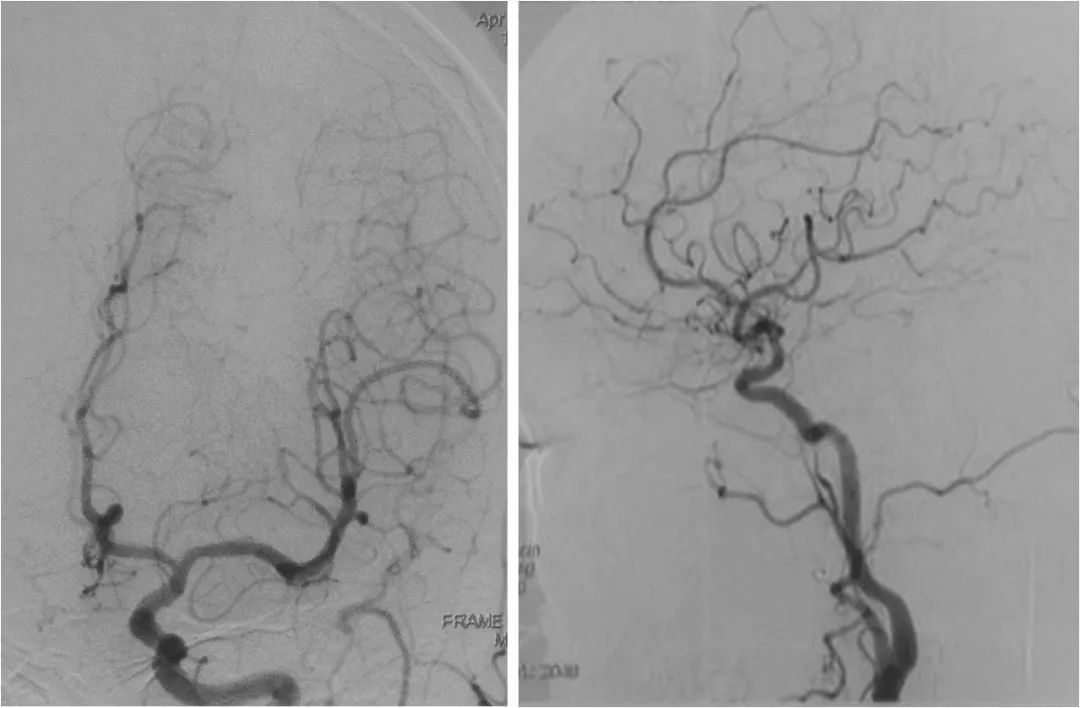

DSA:右大脑中动脉M1段重度狭窄,后循环向前循环代偿欠佳(图7-10)。

图7

图8

图9

图10